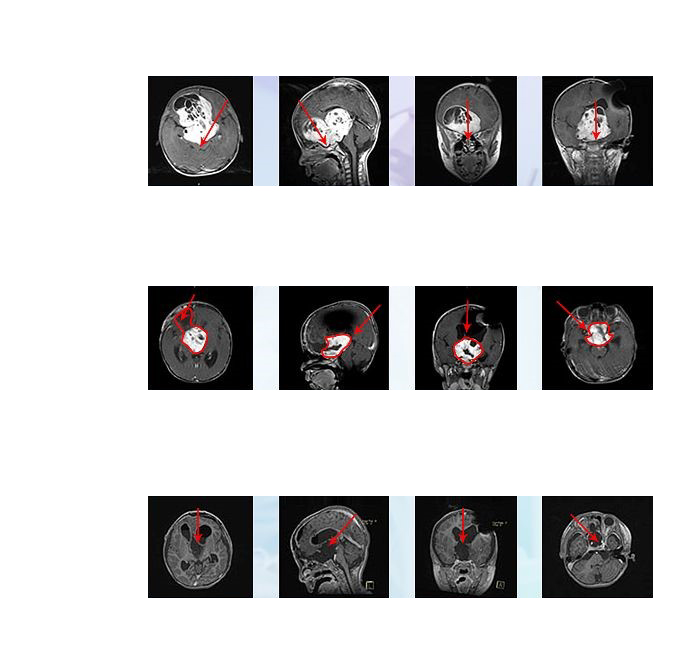

德国的手术之旅较为顺利,巴特朗菲教授通过额骨颅骨开颅术和大脑半球间穹窿入路肿瘤切除术直至Monro孔(室间孔),并沿着脑室壁向中脑行进。小冬右侧的视神经被肿瘤浸润包裹,但是左侧视神经被小心地从肿瘤肿块中剥离出来,垂体腺和垂体柄也被小心的保护起来。

术后患儿有一过性发热和尿崩,均很快控制好转,一周后出ICU病房,术后2周左右患儿视力有轻微好转,2周后出院,且能站立和短距离行走,较入院前好转明显。2019年4月复诊时未见复发,且视力逐渐恢复,可以分辨人影和准确抓拿物品。患儿脑肿瘤得到了大概率以上的切除,术前岌岌可危的视力也保住了。术后病理显示毛细胞型星形细胞瘤,WHO I级,低级别胶质瘤。研究显示其中位生存期可长达50年,肿瘤近全切手术之后可与正常孩子生存时间无异。

此次在德国INI的二次手术,从术前侵袭至双侧额叶及三脑室的较大瘤体,到术后影像上未见瘤体,从几近失明到逐渐地视力恢复接近正常,小冬的手术效果可以说是教科书级的示范案例。